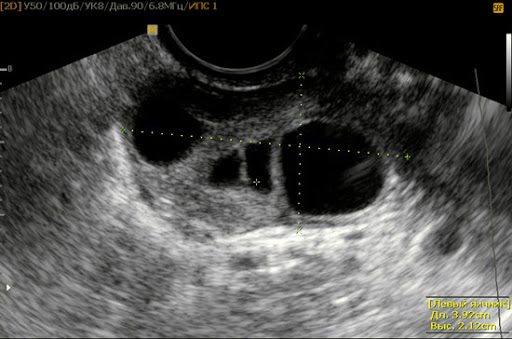

Лечение сальпингоофорита выполняется под надзором гинеколога после подтверждения диагноза. Врач учитывает объективные данные, жалобы пациентки, результаты лабораторных и аппаратных исследований. Девушкам с признаками воспаления маточных труб и яичников назначаются:

При наличии соответствующих показаний врач может настоять на проведении диагностической операции для уточнения локализации абсцесса и осмотра маточных труб.